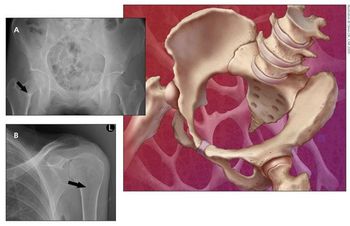

An 81-year-old man with had a one-year history of right knee pain that had worsened in recent weeks despite no trauma or injury. What does the X-ray show?